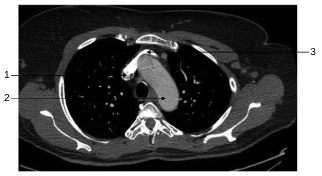

Fig. 35.1 Coupe axiale transverse thoracique passant par l’arc aortique.

1. Veine cave supérieure. 2. Arc aortique. 3. Veine brachiocéphalique gauche.

Source : CERF, CNEBMN, 2022.